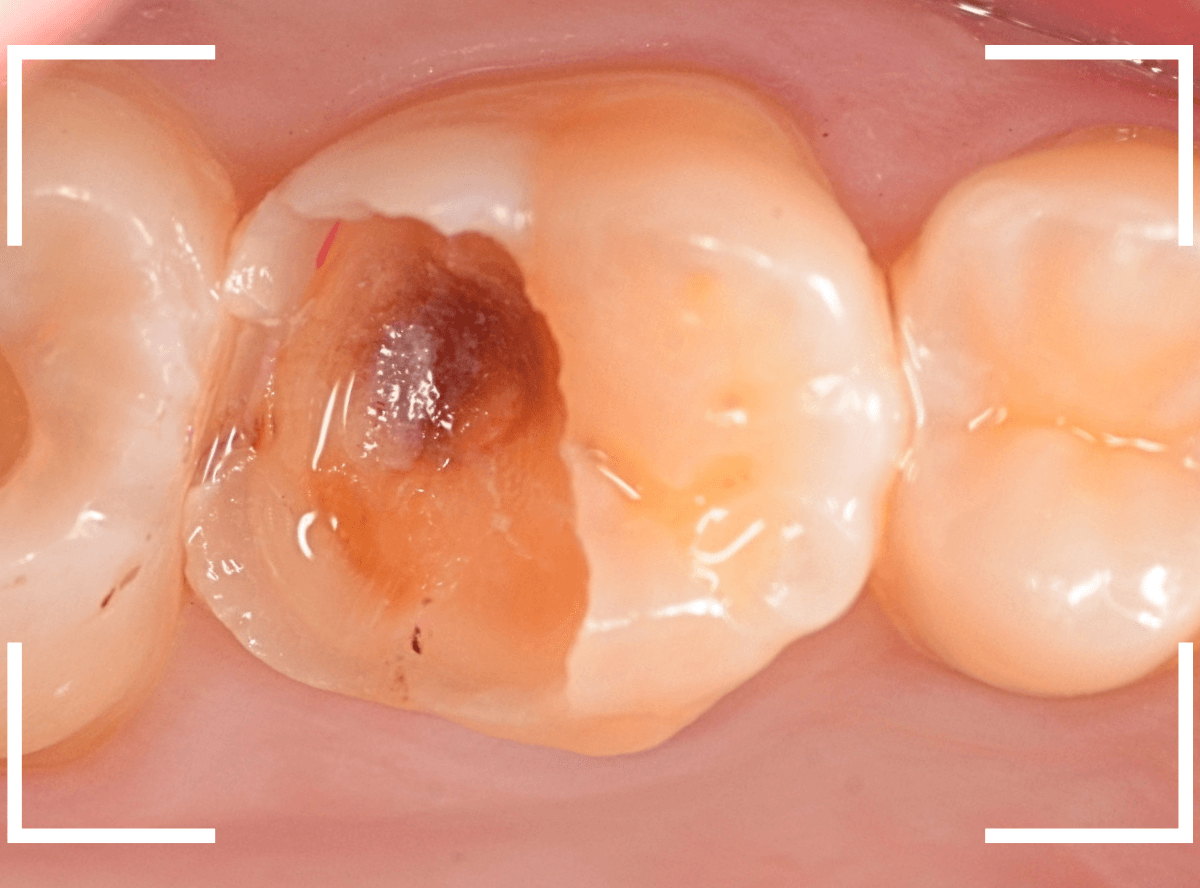

Case.15 レジンの下の深い虫歯

奥歯で咬んだ時に、痛みを感じるという訴えで来院された患者さんです。

パッと見は特に問題なさそうな状態ですが、大きなレジン治療がしてあり、レジンの奥もボヤっと黒っぽく見えてアヤシイ感じです。

麻酔をして、レジンを外します。

レントゲン写真から想定できるような大きな虫歯ですね。

慎重に虫歯を除去します。

赤く染色されている部分が虫歯の残っている部分です。

全ての虫歯を除去したところです。

何とか神経の寸前で虫歯を食い止める事ができましたが、まれに症状が出る事もありますのでお薬をつめてしばらく経過観察します。